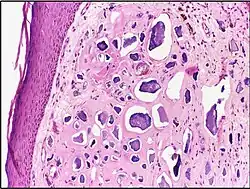

![]() |

Calcinosis cutis | Multiple amorphous basophilic calcium deposits in the dermis. | Category: Histopathology of calcinosis cutis | Calcinosis cutis |